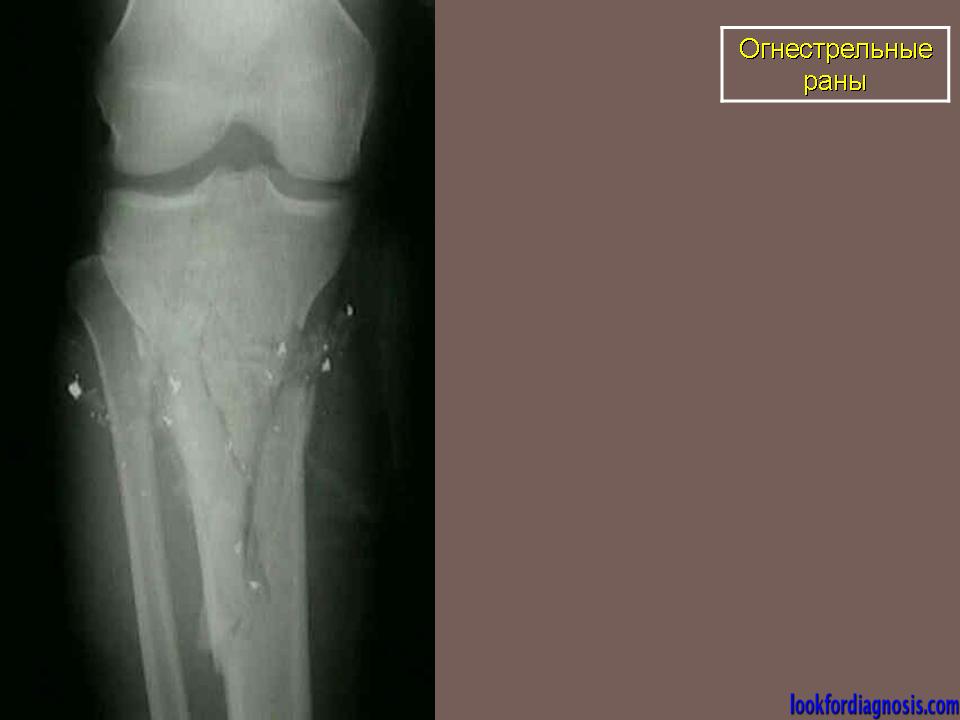

Огнестрельные раны.

Огнестрел и военные действия.